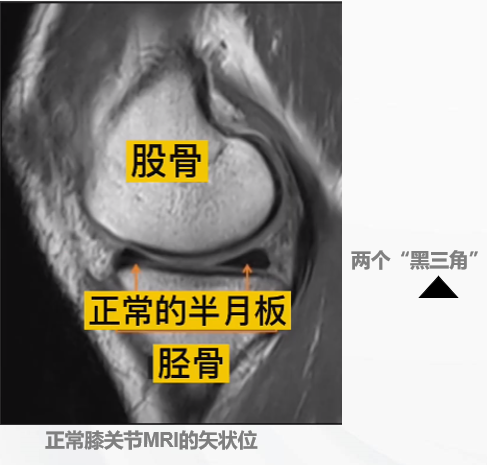

半月板在膝关节MRI上的图像

诊断之三:MRI

半月板损伤的三类信号